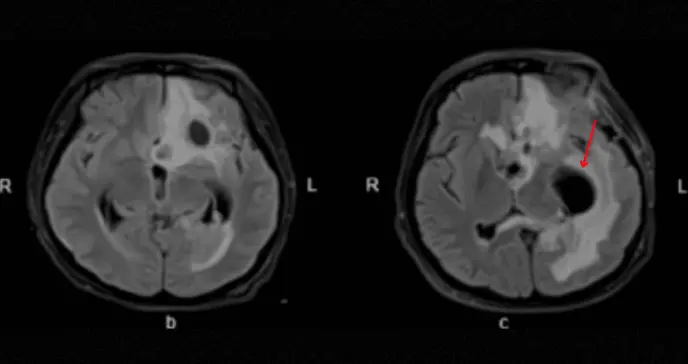

El equipo médico enfrentó un desafío diagnóstico complejo. La resonancia magnética cerebral reveló hallazgos preocupantes: múltiples lesiones con señal anormal en el lóbulo frontal izquierdo y en las astas ventriculares, compatibles con abscesos cerebrales multifocales.

Las imágenes de resonancia magnética seriales demostraron una lenta pero progresiva reducción del tamaño de las lesiones abscesadas y de la inflamación meníngea asociada.